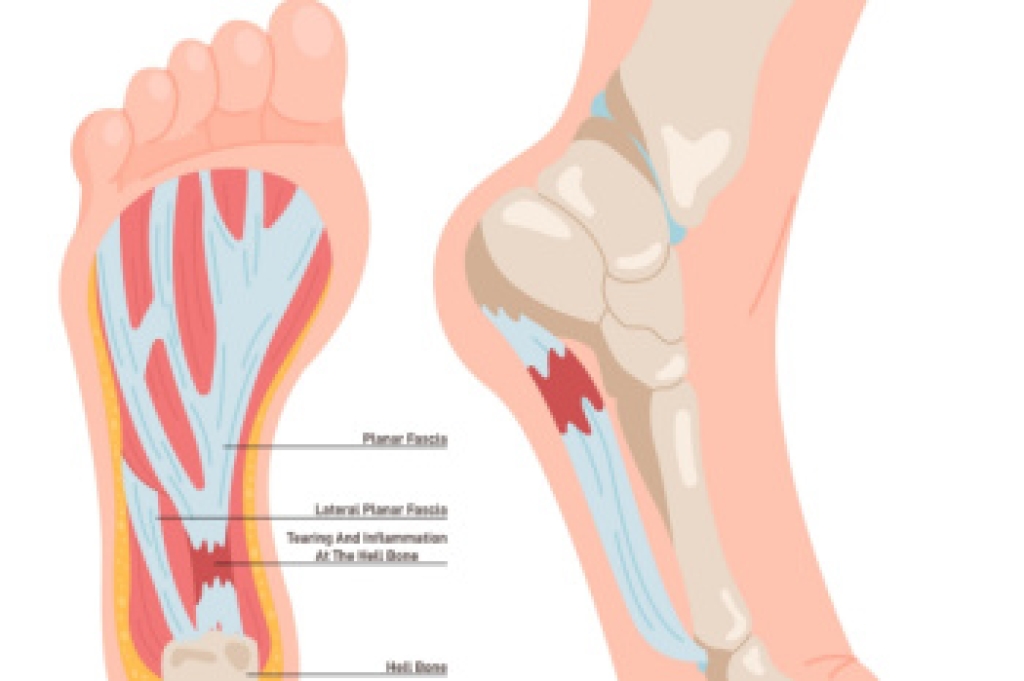

A foot ulcer is an open sore that can affect the surface skin or extend deep enough to reach tendons, bones, or other structures. People with diabetes, poor circulation, nerve damage, or foot deformities face a higher risk of developing ulcers. Nerve damage can make it hard to notice injuries like cuts or pressure spots, especially when wearing shoes that rub against the skin. Poor circulation slows healing by limiting the oxygen that reaches tissues in the foot. If left untreated, a foot ulcer may become infected, sometimes leading to an abscess, cellulitis, or a bone infection. In severe cases, it can cause tissue death or result in limb loss. Early care by a podiatrist focuses on diagnosing the cause of the ulcer, removing dead tissue, if needed, and helping to prevent infection. If you have developed a foot ulcer that will not heal, it is suggested that you schedule an appointment with a podiatrist for an exam and appropriate treatment options.

While it may not seem apparent with small ulcers on the foot, for diabetics, any size ulcer can become infected. Diabetics often also suffer from neuropathy, or nerve loss. This means they might not even feel when they have an ulcer on their foot. If the wound becomes severely infected, amputation may be necessary. Therefore, it is of the upmost importance to properly care for any and all foot wounds.

The best way to care for foot wounds is to prevent them. For diabetics, this means daily inspections of the feet for any signs of abnormalities or ulcers. It is also recommended to see a podiatrist several times a year for a foot inspection. If you do have an ulcer, run the wound under water to clear dirt from the wound; then apply antibiotic ointment to the wound and cover with a bandage. Bandages should be changed daily and keeping pressure off the wound is smart. It is advised to see a podiatrist, who can keep an eye on it.